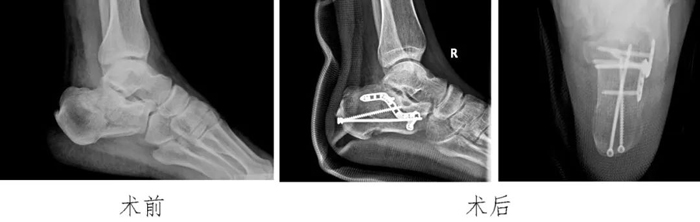

3?跟骨骨折:

利用改良跗骨竇切口微創(chuàng)治療跟骨骨折,術(shù)后康復(fù)時(shí)間縮短。